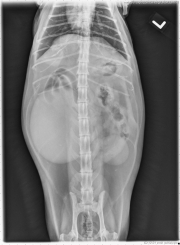

The right kidney is markedly enlarged, with a rounded shape. It is distorting the abdominal wall on the v/d projection and displacing the ascending and transverse colon medially and ventrally. The left kidney also has an abnormal shape, with reduced length and increased width.

There is also spondylosis deformans at the L5-6 intervertebral disc space, which is an incidental finding.

Bilateral perinephric pseudocysts and chronic renal disease.